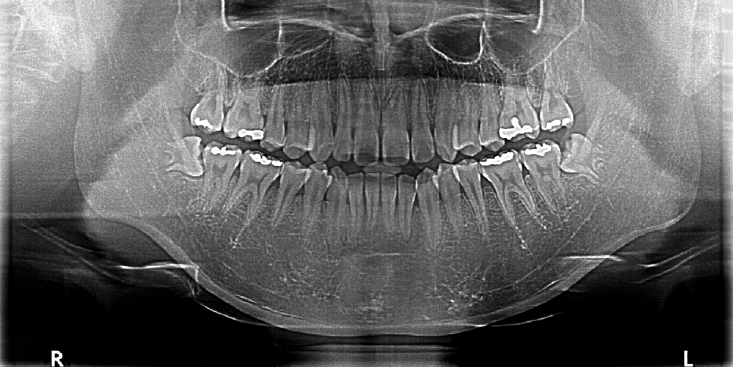

Figure 4.

Postoperative panoramic radiograph showing extraction sites of mandibular third molars with no evidence of pathologic bone changes.